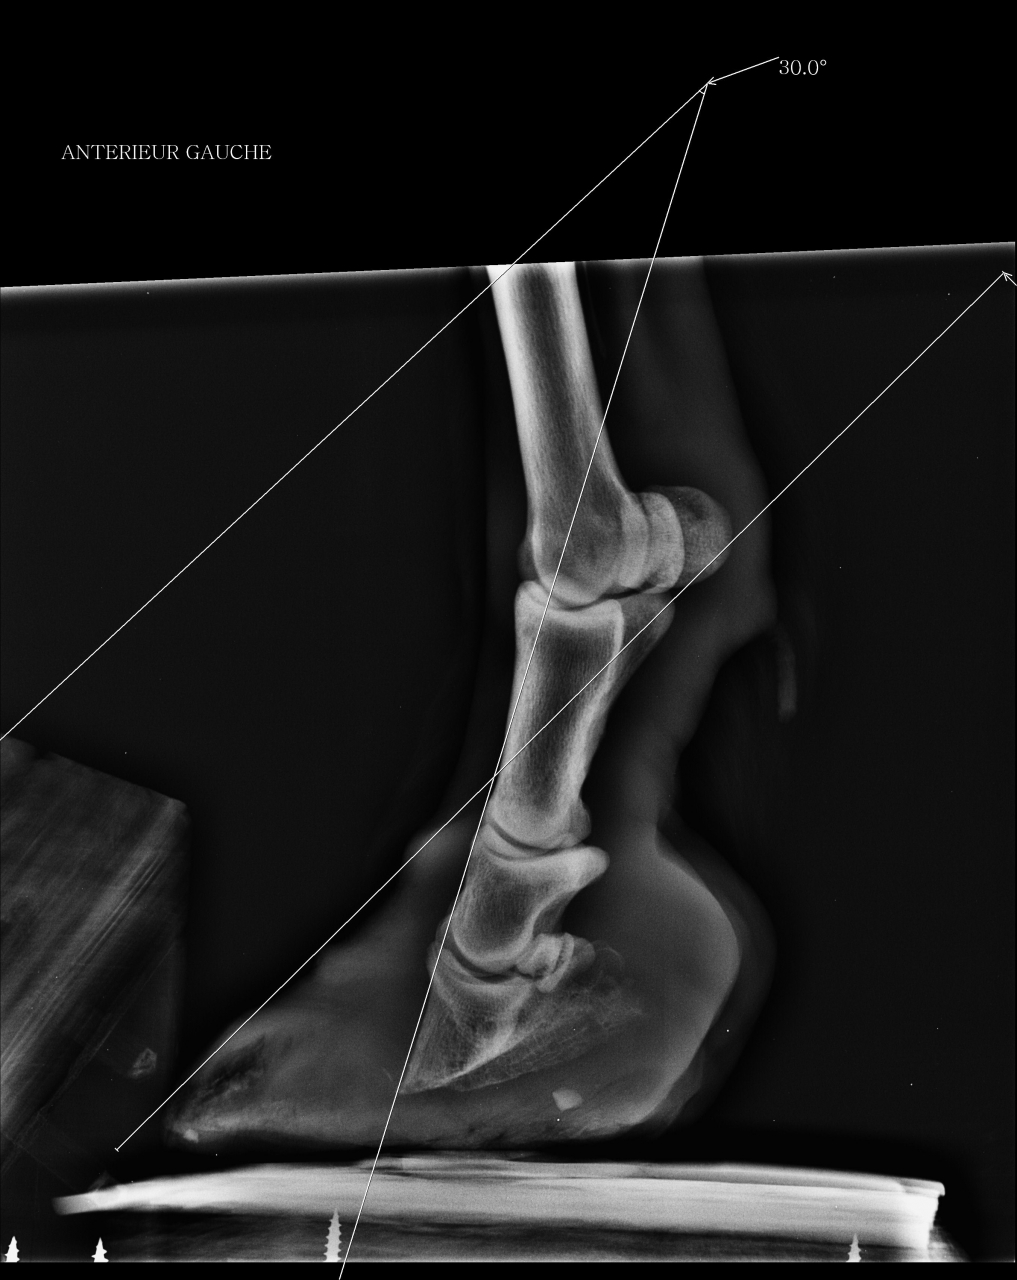

DéconnectéDire merci | Bonjour, Je viens vers vous pour ma vieille ponette (âgée aux alentours de 30 ans) que j’ai recueillie en février 2014 qui est atteinte du syndrome de cushing et a une fourbure chronique avec bascule de la 3ème phalange de 30° pour les 2 antérieurs. En juin dernier (8 juin 2015), lors de son dernier parage alors que seule la pince a été rognée et les talons abaissés d’un ½ cm, elle est tombée dans une souffrance terrible, à rester couchée et à ne se relever que pour manger et faire ses crottins, j’ai cru la perdre. C’est cela qui m’a poussé à faire des radios (qui ont été faites donc 3 semaines après le parage) ; Les radios ont révélé une bascule de la 3ème phalange de 30° sur les 2 antérieurs. Bien sûr pour les vétos qui la suivent, la seule proposition a été l’euthanasie mais ma ponette s’est battue car elle a envie de vivre et moi je me bats à ses côtés. Elle a commencé à aller mieux lorsque ses pieds ont commencé à repousser après 2 mois vers fin juillet début aout ; au lieu d’une souffrance continue, elle a mal seulement lorsqu’elle se déplace (elle se déplace très peu, tout son petit paddock est recouvert d’un épais tapis de paille ; elle a un régime adapté avec plusieurs rations réparties sur la journée composées d’un mélange de foin haché et granulés de paille réhydratés de sorte que le taux de sucres ne dépasse pas 5%). Le maréchal qui la suivait, pareur naturel et ancien maréchal, m’a lâché en aout car il n’a pas voulu admettre, comme beaucoup de maréchaux ferrants que j’ai contactés pour avoir des avis, que ma ponette ne retrouverait pas un fonctionnement normal des pieds et que le mieux pour elle était de lui laisser du pied et lui faire seulement un parage « antalgique » adapté à son cas, de façon à lui permettre de continuer sa petite vie avec le moins de douleur possible. Lui abaisser les talons, lui faire un parage type parage naturel ne l’entrainerait que vers des douleurs insupportables avec le risque qu’elle succombe à ces douleurs. Je me suis battue depuis aout pour trouver un maréchal compétent qui veuille bien se déplacer et un maréchal a enfin accepté de venir la semaine prochaine ; mais pendant ses 4 derniers mois les pieds de ma ponette ont énormément poussé et sont en babouche mais étonnamment elle n’a pas plus mal lorsqu’elle se déplace que les mois précédents lorsque ses pieds n’avaient pas encore atteint ce stade critique en babouche (Croyez moi ça me rend folle d’en être arrivé là, tout aurait pu être tellement plus simple et occasionner moins de souffrance si le pareur naturel en aout avait accepté de se contenter de faire un entretien des pieds…). Je voulais préciser que lorsque ma ponette se déplace, elle prend appui sur la pince en arquant les membres (elle s’est toujours déplacée ainsi quelque soit la taille de ses pieds). Bien sûr maintenant avec ses pieds en babouche, elle a les glomes proches du sol et c’est son talon qui lui sert de voute plantaire, la sole remontant vers l’avant presque perpendiculairement au sol… Je me pose la question de savoir comment se positionne la 3ème phalange maintenant dan un tel pied. En fait, je me pose beaucoup de questions car j’ai peur, très peur que l’intervention de la semaine prochaine sur ses pieds, même si le parage sera léger car il est hors de question de redonner en une seule intervention, une forme normale à ses pieds, n’entraine à nouveau mon petit bout de ponette vers une souffrance terrible, dont je sais cette fois qu’elle ne se remettra pas…elle me le fait comprendre à sa manière, à savoir que pour qu’elle me donne un de ses antérieurs, je dois négocier bien 10 min, cela lui engendre un stress important avec accélération de la respiration et bien sûr je dois lui prendre et aussitôt le reposer, juste le temps de lui déposer une compresse imbibée de liqueur de villatte car la corne sous ses pieds pourrie. Peut-on la laisser avec ses pieds en babouche pour éviter le risque de la replonger dans une douleur insupportable en touchant même si peu que ce soit à ses pieds ? Y-t-il vraiment un risque qu’elle replonge dans la douleur si on se contente simplement de rogner la partie en babouche ? Voilà, je vous remercie vraiment par avance pour votre aide, vos conseils et vos témoignages. Je vous joins des photos et radios de ses pieds. Désolée du pavé… radio antérieur droit ![]() radio antérieur gauche ![]() photos après parage juin 2015 ![]() ![]() photos septembre 2015 ![]() photos aujourd'hui ![]() ![]() |

| Dire merci | Quand on regarde les radios, le confort s'explique par une position alors "normale" des phalanges, donc moins de tension dans les tendons etc... mais ça fait mal au bide à voir... sauf que le mal au bide est du côté de l'humain et le "confort" est du côté poney... |

Déconnecté | Si elle est bien en babouches, c'est parce que sa phalange se trouve à la "bonne place" pour le coup...et donc elle est bien. Il ne faut pas, enfin plutôt il ne faut plus chercher à redresser tout ça. Ne pas oublier qu'il y a sans doute de l'arthrose la dedans. Je pense que le maréchal se contentera ou devra se contenter de rogner ce qui est en trop, et donner des conseils pour nettoyer si besoin est (genre bains de pied dans un pediluve par ex, la faire marcher dedans). Pour ma part je ne trouve pas qu'elle aille contre la santé de la ponette, s'il fallait piquer un cheval à chaque crise, on serait pas rendu. Elle a les moyens de la soulager, elle fait tout ce qu'elle peut (y' en a pas beaucoup qui y iraient jusque-là) et si la ponette a souffert à ce point...c'est parce qu'elle a eu un parage raté, et à 30 balais avec une telle bascule, ça pardonne pas. Il faut la soulager autant que possible, mais le jour ou on ne pourra plus rien faire, même son moral semble bon, il ne faut pas aller plus loin. Même si on souhaite gagner 3 jours, ou 3 semaines, cela peut être 3 jours ou 3 semaines d'enfer. |

DéconnectéDire merci | Si elle est bien en babouches, c'est parce que sa phalange se trouve à la "bonne place" pour le coup...et donc elle est bien. Phoeb, pouvez vous préciser ? Vous voulez dire que la 3ème phalange est parallèle au sol ? par rapport à cette question, le maréchal qui doit venir n'a pas su répondre et une des vétos qui la suit m'a dit que la 3ème phalange était comme sur la radio en alignement avec les phalanges 1 et 2 et piquait toujours vers le sol dans son pied en babouche. |

Déconnecté | Lara129: oui c'est ça, phalange parallèle au sol. Mais attention, c'est juste une idée, enfin plutôt une interrogation à étudier avec le maréchal. La pointe de la phalange dans la sole ça fait une grosse pression sur un endroit très réduit donc forcément douloureux. Et la position de la ponette influant sur la forme de la pousse des pieds pour se soulager elle a peut être (sûrement?) trouvé un moyen de repartir la pression sur une plus grande surface. Alors certes ça pourrit c'est moche et ça fait maltraité, mais si elle mieux ainsi qu'avec des pieds normaux à son âge, je pense que c'est le mieux. Tu as fait endorment de choses pour elle en tout cas, je tiens à te dire bravo, j'admire vraiment tout ce que tu as fait pour elle, c'est un geste magnifique. Et tu n'as pas à t'en vouloir d'avoir fait tel ou traitement, on ne peut jamais savoir ce qui peut arriver à l'avance. |